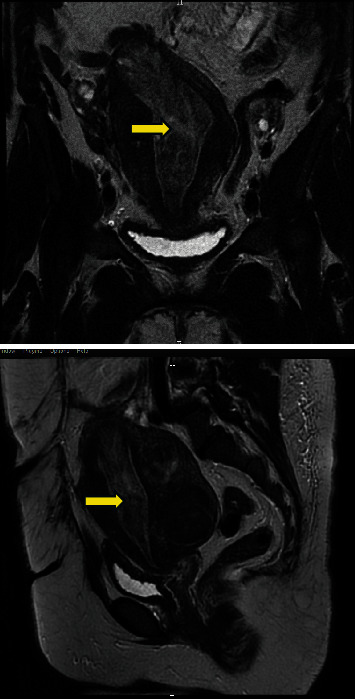

Introduction: Uterine leiomyomas are a frequent finding in women of reproductive age. However, rare, unusual growth patterns exist, such as atypical, cellular, mitotically active, myxoid, and epithelioid leiomyomas, and present a major concern as they mimic highly malignant uterine tumors such as uterine leiomyosarcomas. An example of such cases is the epithelial type leiomyoma which is the subject of our report in a 35-year-old female. Case: A 35-year-old, nulliparous lady presented with abnormal uterine bleeding to the emergency department. Workup revealed a suspicious uterine mass that was extending from the intramural part of the fundus down the cervical os. The patient was managed by open myomectomy without complications. The final pathology report revealed an extremely rare benign epithelial type leiomyoma, no malignancy, areas with minimal atypia and low mitotic activity (< 5/10 high power fields), and areas of focal necroses (possibly ischemic type) were seen. No coagulative tumor necrosis was noted. Conclusion: Uterine leiomyomas are a common pathology of the uterus that can be confused with malignant tumors, especially in the setting of unusual growth patterns such as the epitheloid leiomyomas. Definitive management involves myomectomies with regular follow-up with favourable prognosis. It is important to properly manage these cases to avoid the overdiagnosis and mistreatment not to mention the repercussion of false diagnoses on the patient's mental health and well-being.